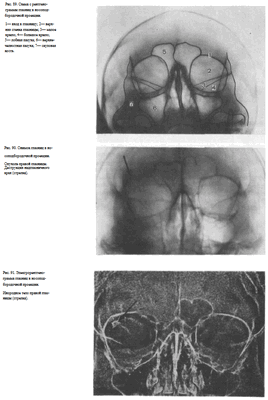

УКЛАДКИ СНИМОК ГЛАЗНИЦЫ В НОСОПОДБОРОДОЧНОЙ ПРОЕКЦИИ

Назначение снимка. Изучение состояния костей, образующих вход в глазницу, костной структуры верхней и наружной ее стенок.

Укладка больного для выполнения снимка сходна с укладкой для выполнения обзорного снимка в этой же проекции. В данном случае используюткассету размером 13X18 см, располагая ее в кассетодержателе в поперечном положении. Больной прилежит к столу подбородком и кончиком носа,переносье соответствует центру кассеты. Центральный пучок излучениянаправляют на центр кассеты. Фокусное расстояние—100 см.

В этой же укладке может быть выполнен снимок одной (правой или левой) глазницы. В таких случаях центр снимаемой глазницы соответствует центру кассеты, и на него отвесно направляют пучок излучения, используя тубус или диафрагмирование пучка излучения с помощью щелевой диафрагмы. Фокусное расстояние—100 см (рис. 88).

Информативность снимка. На снимке хорошо видны вход в глазницу, структура ее стенок, иногда малое и большое крыло клиновидной кости (рис. 89). На снимке в этой проекции могут быть выявлены деструктивные изменения стенок глазницы и инородные тела в ее полости (рис. 90, 91). Для выявления изменений в области верхней стенки глазницы (например, при

диагностике переломов) снимок целесообразно выполнять не в носоподбородочной, а в подбородочной проекции.

На прицельном снимке каждой из глазниц в этой же проекции, как правило, небольшие изменения структуры стенок, а также мелкие инородные тела глаза видны лучше. Такие снимки широко используют в офтальмологической практике (рис. 92).

Критерии правильности технических условий съемки и правильности укладки основываются на четкости выявления костной структуры и симметричности изображения глазниц.

Наиболее частые ошибки при выполнении снимка сводятся к асимметрии положения головы.